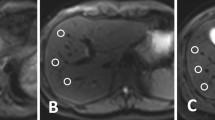

In 1 of the 28 patients of group A, a total of 2/101 FLLs (5 and 4 mm in diameter) were not detected on L1-DWI, but on the patient’s conv-DWI. Even in retrospect, these two FLLs were not visible on L1-DWI. An analysis of why these two FLLs were occult on L1-DWI showed that one FLL happened to be obscured by pulsation artefacts at the site of the FLL on L1-DWI. For the other missed FLL, no apparent reason could be identified (Fig. 4A).

Patients of both groups with FLLs missed in L1-DWI. (A) 47-year-old female patient of group A who underwent a liver MRI for staging of colorectal carcinoma. In conv-DWI (upper row left), a FLL was detected in segment VII, that was not prospectively called on L1-DWI (upper row right). Taking all sequences from the routine MRI into account, e.g. T2-TSE (lower row left) and eTHRIVE (lower row right), this FLL corresponded to a cystic transformed metastasis. conv-DWI = single-shot EPI-based DWI with parallel imaging reconstruction. L1-DWI = single-shot EPI-based DWI with L1-regularized iterative reconstruction. T2w-TSE = T2-weighted turbo-spin echo. eTHRIVE = enhanced high-resolution fat-suppressed pulse sequence. (B) 46-year-old female patient of group B who underwent a liver MRI for staging of cervical carcinoma. In conv-DWI (upper row left), a FLL was detected in segment V, that was not prospectively called on L1-DWI (upper row right). Taking all sequences from the routine MRI into account, e.g. T2-TSE (lower row left) and eTHRIVE after injection of Gadobutrol (lower right right), this FLL corresponded to a thrombosed liver hemangioma. conv-DWI = single-shot EPI-based DWI with parallel imaging reconstruction. L1-DWI = single-shot EPI-based DWI with L1-regularized iterative reconstruction. T2w-TSE = T2-weighted turbo-spin echo. eTHRIVE = enhanced high-resolution fat-suppressed pulse sequence.

In 4 of the 47 patients of group B (6%), 9/248 FLLs (4%), between 3 and 7 mm in diameter, were not prospectively detected on L1-DWI, but prospectively called on the respective patient’s conv-DWI. Even in retrospect, these lesions were not visible on L1-DWI (Fig. 4B). An analysis of why the FLLs were occult on L1-DWI did not yield a definitive reason; in particular, there was no image degradation due to motion or pulsation artefacts at the site of the FLLs that would explain why FLLs were not visible.